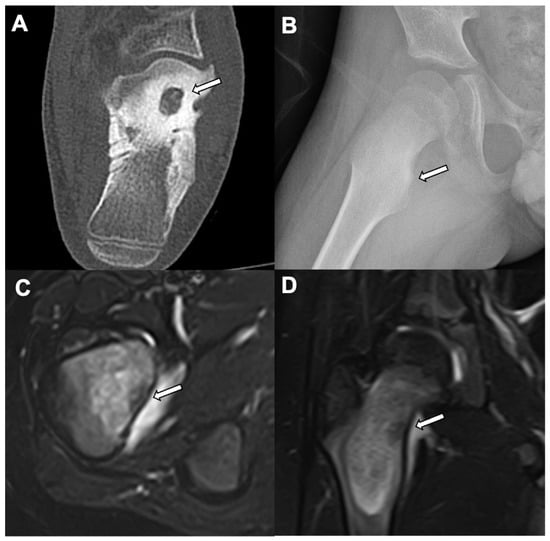

6. Osteoblastoma

- Kroon, H.M.; Schurmans, J. Osteoblastoma: Clinical and radiologic findings in 98 new cases. Radiology 1990, 175, 783–790. [Google Scholar] [CrossRef]

- Lucas, D.R.; Unni, K.K.; McLeod, R.A.; O’Connor, M.I.; Sim, F.H. Osteoblastoma: Clinicopathologic study of 306 cases. Hum. Pathol. 1994, 25, 117–134. [Google Scholar] [CrossRef]

| Radiographic/CT features | Juxtacortical, well-circumscribed homogenous sclerotic lesion | Homogenous intra-medullary sclerotic focus with spiculated margins | Small (less than 2 cm) cortical lucency with extensive surrounding sclerosis | Expansile large (more than 2 cm) lucent lesion with matrix mineralization |

| Treatment | None if asymptomatic; excision if complications related to mass effect | None | Percutaneous CT guided radiofrequency ablation | Surgery or percutaneous CT guided ablation |